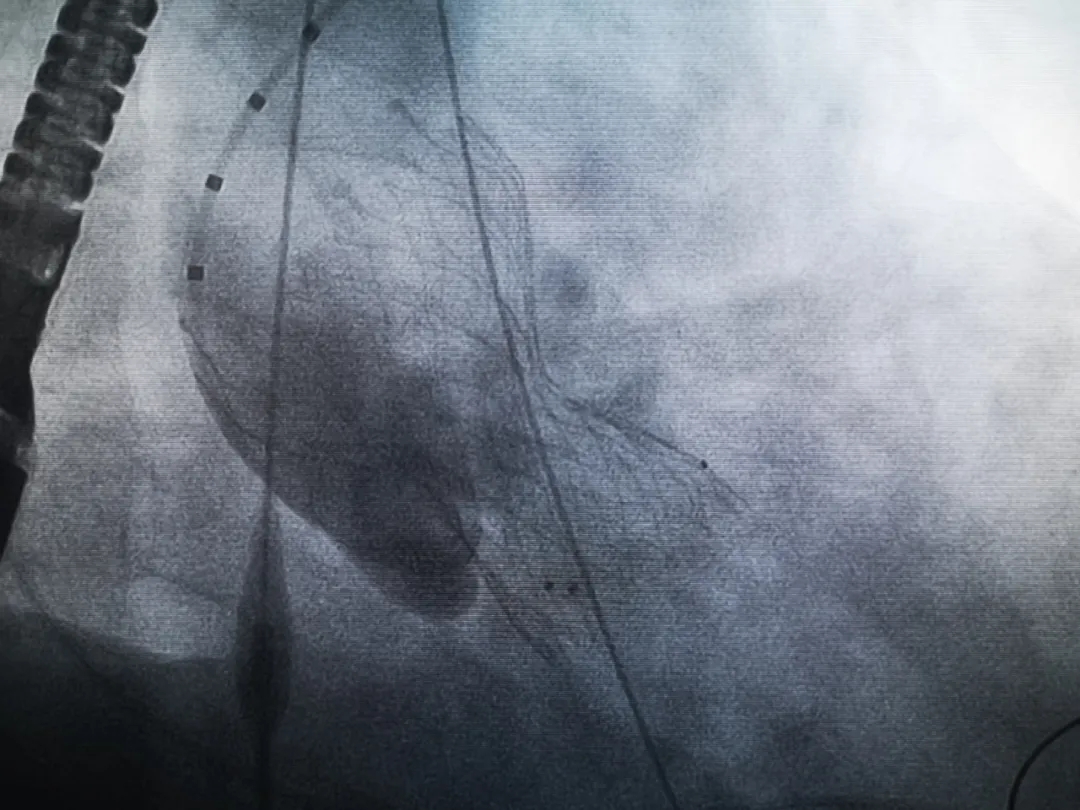

王子的手術(shù)被安排在周五。術(shù)前一天,TAVR團(tuán)隊(duì)再次碰頭討論,從麻醉中血壓控制、球囊擴(kuò)張、瓣膜釋放,到各種可能突發(fā)狀況的應(yīng)對,都提前制定了方案。尤其是瓣膜鈣化極為嚴(yán)重,對于擴(kuò)張球囊型號的選擇、擴(kuò)張的力度以及瓣膜植入后瓣周漏的發(fā)生預(yù)測,都具有很大挑戰(zhàn)。然而,如果沒有這些挑戰(zhàn),他又何必選擇我們呢!

手術(shù)過程緊張而有序,心臟沒有停跳,也沒有太大的血壓波動(dòng);球囊擴(kuò)張的恰到好處,瓣膜釋放之后超聲醫(yī)生的評估是至關(guān)重要的,因?yàn)槲覀兲崆熬蜏?zhǔn)備了后擴(kuò)張,也準(zhǔn)備了瓣中瓣,甚至還準(zhǔn)備了瓣周漏封堵。所幸的是,超聲診療中心劉夢梅醫(yī)生說:沒有返流、沒有瓣周漏,瓣膜形態(tài)良好,跨瓣壓差約17mmHg(相較于術(shù)前的87mmHg還是可以接受的)。瓣膜置入的成功并不是慶祝的時(shí)候,從戰(zhàn)場撤退仍然需要謹(jǐn)慎。由于王子特別胖,腹股溝區(qū)脂肪尤為肥厚,在股動(dòng)脈插管拔除、確認(rèn)搏動(dòng)正常之后,便逐層縫合。同時(shí)為了美觀、縫合之后不至于鼓個(gè)包出來,我們又仔細(xì)剪除了部分脂肪。術(shù)后次日,王子便可以下床活動(dòng)了。